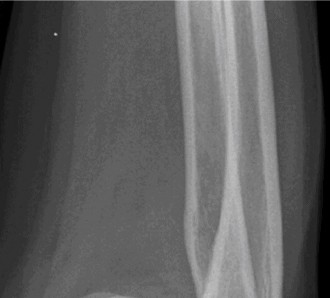

Treat a patient with scapular winging? CASE 23 A 47-year-old, right-hand-dominant male presents to your clinic complaining of right shoulder weakness for the past 2 months. He denies any history of trauma but notes sudden onset of pain 2 months ago that lasted approximately 2 weeks and then subsided without any intervention and was followed by shoulder weakness. He works as a lawyer and has been going through a divorce for the past year. Physical examination reveals no tenderness to palpation about the shoulder. He has decreased sensation over the lateral aspect of the shoulder, decreased muscle bulk over the left shoulder compared with the contralateral side, and weakness with left shoulder abduction. He is distally neurovascularly intact. The patient had already been referred for an x-ray and MRI by his primary care doctor that are shown in Figures 2–62 and 2–63.

Figure 2–62

Figure 2–63

The correct answer is (C). The patient’s decreased sensation over the deltoid, deltoid muscle atrophy on examination, and MRI with atrophy of the teres minor points to axillary nerve dysfunction. Suprascapular nerve injury (Choice A) would result in atrophy of the infraspinatus and or infraspinatus muscles, leading to weakness with external rotation and/or forward flexion. Dorsal scapular nerve injury (Choice B) would result in weakness of the rhomboid muscles and levator scapulae. While injury to the posterior cord of the brachial plexus (Choice D) would result in symptoms of axillary nerve palsy, they would also involve dysfunction of the radial nerve, which also comes off the posterior cord.

The correct answer is (B). Parsonage Turner syndrome (brachial neuritis) is characterized by acute brachial neuropathy which can affect different nerves of the brachial plexus. In this patient, it is the most likely explanation for his atraumatic deltoid paralysis with axillary nerve palsy in a time of severe stress. The cause of Parsonage Turner Syndrome is unknown, but it has been associated with severe stress and viral infection. Quadrilateral space syndrome (Choice A) involves entrapment of the axillary nerve as it passes through the quadrilateral space, would present as chronic dull pain, and is usually not associated with decreased sensation. While Choices C and D can both be a cause of axillary nerve injury, the patient has no history of trauma and there are no masses on his MRI.